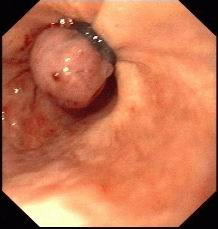

①胃镜

正常十二指肠

正常胃体

正常胃角

正常食管

反流性食管炎

霉菌性食管炎

食管CA

胃角溃疡

胃镜检查术,俗称胃镜,是目前诊断上消化道(食管、胃、十二指肠)疾病最好的方法,对病变的观察清晰度优于任何其它影像技术,同时能对病变进行活体组织检查获得病理学诊断,并对早期上消化道癌、出血、狭窄、息肉等各种病变进行内镜下微创治疗术。我院消化内镜是省内开展胃镜及镜下微创治疗较早的单位,拥有最完善、最先进的内镜操作系统,每年完成胃镜诊治3万多例次。胃镜检查术简单、安全性好。大部分上消化道癌发现已经中晚期,因为多数早期消化道癌没有独特的表现,只有通过胃镜检查才能得到确切的早期诊断。50%早期消化道癌能够在胃镜下行局部病灶切除术(EMR、ESD),术后生存率可达90%。